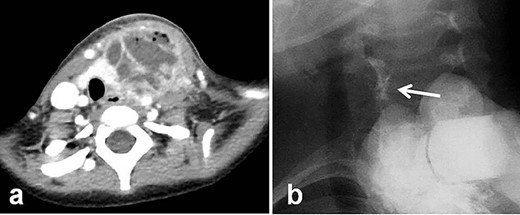

A 4-year-old girl was admitted with left neck swelling. The physical findings showed a huge mass with erythema in the left neck. Enhanced computed tomography showed a large abscess (Fig. 1a). After incision and drainage, a barium swallow examination and direct fistulography from the wound showed no fistula. Five months later, she was hospitalized for the second time for left neck swelling. After incision and drainage, a direct fistulography from the wound showed a fistula from the abscess cavity to the left pyriform sinus (Fig. 1b). She was diagnosed with a pyriform sinus fistula (PSF). She was followed in the outpatient clinic with serial ultrasonograms for elective surgery, but after 5 months, she was readmitted with recurrent left neck swelling before surgery was scheduled. Thus, she underwent an open-neck surgical procedure for recurrent PSF. First, the catheter was inserted into the opening of the fistula through an endoscope and contrast medium was injected, which did not reveal a fistula from the left pyriform sinus to the abscess cavity. Next, after direct injection of contrast medium and indigo carmine into the abscess cavity, an open-neck surgical procedure was performed with coring out of the stained fistula, but a fistula was overlooked near the upper lobe of the left thyroid, and the scar tissue with abscess was removed (Fig. 2a–c). Finally, a guide wire was successfully inserted through the endoscope into the fistula; the wire was gripped with forceps under fluoroscopic guidance and removed (Fig. 3a and b). As a modification of the surgical approach and treatment for the orifice of the PSF, a catheter was exchanged through the guide wire, and a nylon thread was passed into the catheter (Fig. 3c and d). The tip of the nylon thread from the oral side was fastened and fixed to a gauze ball (Fig. 4a and b) [9]. After removing the nylon thread, the gauze ball was also removed and the orifice of the PSF was noted (Figs 3e, f and4c, d). The orifice of the PSF was doubly closed with absorbable sutures of the thropharyngeal and cricopharyngeal parts of the inferior constrictor of the pharynx (Fig. 5). She was discharged uneventfully and doing well without a recurrence 12 months postoperatively.

Radiologic examinations. (a) Enhanced computed tomography showing a huge abscess. (b) At the second hospitalization, direct fistulography from the wound showed an obvious fistula from the abscess cavity to the left pyriform sinus (white arrow: fistula).